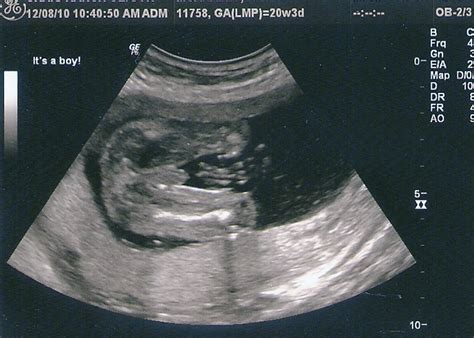

The 20 week sonogram is often referred to as the "anatomy scan" or the "mid-pregnancy ultrasound," and for good reason—it is arguably the most significant milestone of your prenatal journey. Around the halfway mark of your pregnancy, this diagnostic procedure provides a comprehensive look at your developing baby, checking everything from physical growth to organ function. It is a moment filled with anticipation, nerves, and excitement, as it is often the first time you get a truly clear, detailed view of your little one’s features, movements, and perhaps even their sex.

When you arrive for your 20 week sonogram, you can expect the appointment to take anywhere from 30 to 60 minutes. The technician, or sonographer, will use a transducer—a handheld device that emits high-frequency sound waves—to create images of the fetus on a monitor. Because the baby is larger and more developed than in previous scans, the images will be significantly more detailed.

The primary goal of this scan is not just to see the baby, but to ensure that everything is developing according to the expected physiological standards. The sonographer will systematically examine the baby from head to toe, checking various markers of health and growth.